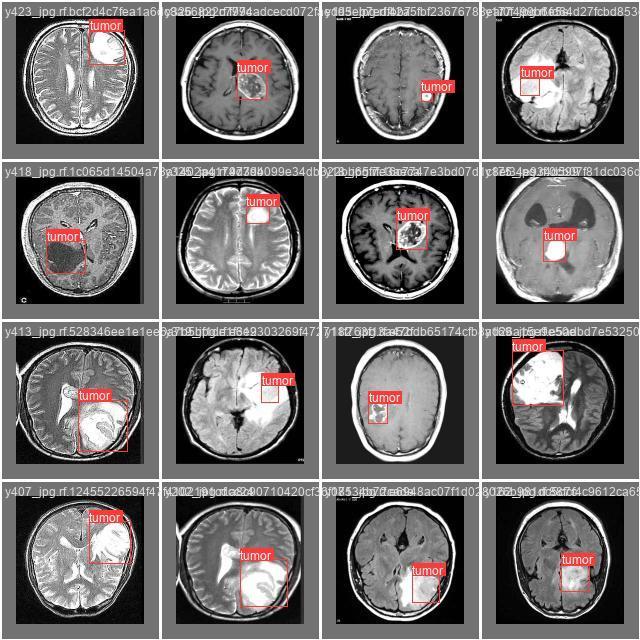

ThevisualizationpresentedinFig. 7depictsthebounding box predictions made by the model, effectively highlighting the precise localization of tumors in the MRI scans. The bounding boxes superimposed on the images reflect the model's capability to accurately outline tumor areas; however, there is a notable density of overlapping boxesinthecentralregionoftheimage.